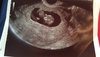

Gratulacje [emoji173]️ Jaki piękny maluszek [emoji173]️[emoji173]️ Już się nie mogę doczekać jak mój będzie wyglądać jakkolwiek człowieczo[emoji23]Kochane ja juz po wizycie [emoji173][emoji173]jestem zakochana[emoji173][emoji173]wszystko ok maluszek tak się wiercił machał rączkami i nóżkami[emoji173]że lekarz zdjecia zrobić nie mógł hehe ale się udało![]()